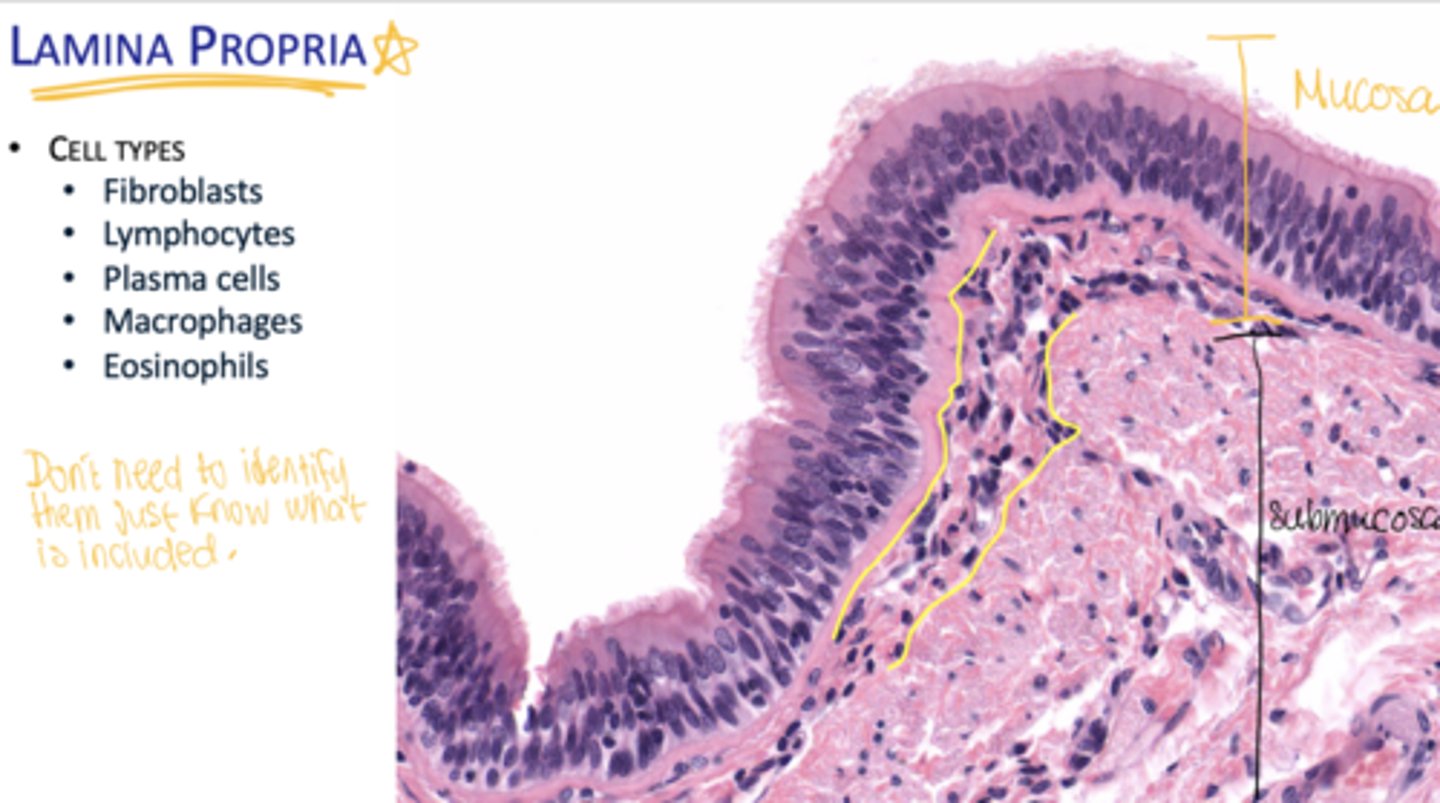

What layers make up the mucosa?

Epithelium, basal lamina, and lamina propria.

What cells are found in the lamina propria?

Fibroblasts, lymphocytes, plasma cells, macrophages, eosinophils.